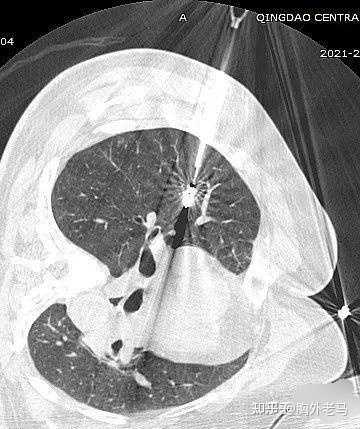

另外,生气的人更容易导致免疫功能低下,免疫功能受损,容易引起肺结节。那么中医如何解决这种“气怒”的肺结节人群呢?分享几个案例。案例1:马先生,65岁,吸烟30多年。2020年7月,因胸闷、胸痛、憋气等症状到医院就诊。CT检查后显示双肺多发结节。左肺下叶胸膜下有较大的实性结节,直径约6 mm,未给予其他治疗。

2019年初,一个很冷的早晨,她感冒起床,咳嗽,痰中带血。在家人陪同下,到中国人民解放军总医院海南分院复查。CT结果显示左肺上叶纵隔及胸膜下见斑片,边界不清。双肺下叶增加一个直径约7mm的磨玻璃小结节,边界清晰。这次陈女士慌了,担心是肺癌。她想马上手术切除肺结节,但很多医生都拒绝了。医生说很可能是良性的,建议随访。

肺结节是指患者肺部的肿块小于3 cm。首先,只需要区分肺结节是良性还是恶性。此时建议患者到医院诊治,做胸部ct检查或通过支气管镜或经皮肺穿刺做一个病理检查,诊断肺结节的性质。然后通过区分良恶性程度给予患者相应的治疗。扩展信息;1.肺结节为小灶状、类圆形阴影,影像密度增高,可单发或多发,无肺不张、肺门肿大和胸腔积液。